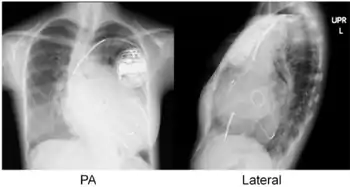

Cardiac resynchronisation therapy (CRT or CRT-P) is the insertion of electrodes in the left and right ventricles of the heart, as well as on occasion the right atrium, to treat heart failure by coordinating the function of the left and right ventricles via a pacemaker, a small device inserted into the anterior chest wall.[1]

CRT requires the placement of an electrical device for biventricular pacing, along with placement of (at least) two pacing leads, to facilitate stable left ventricular and right ventricular pacing. For all elements, the first stage of the process is local anaesthetic followed by incision to allow for approach from the appropriate vein. From here, the leads and device can be inserted.[1]

Device placement

The device is inserted in a subcutaneous pocket created by the surgeon, the choice of left or right side of the chest wall is determined mainly by the patient's preference or location of preexisting device. The device, similar to that of a traditional pacemaker, is generally no larger than a pocket watch and has inserts for the electrode leads.[1]